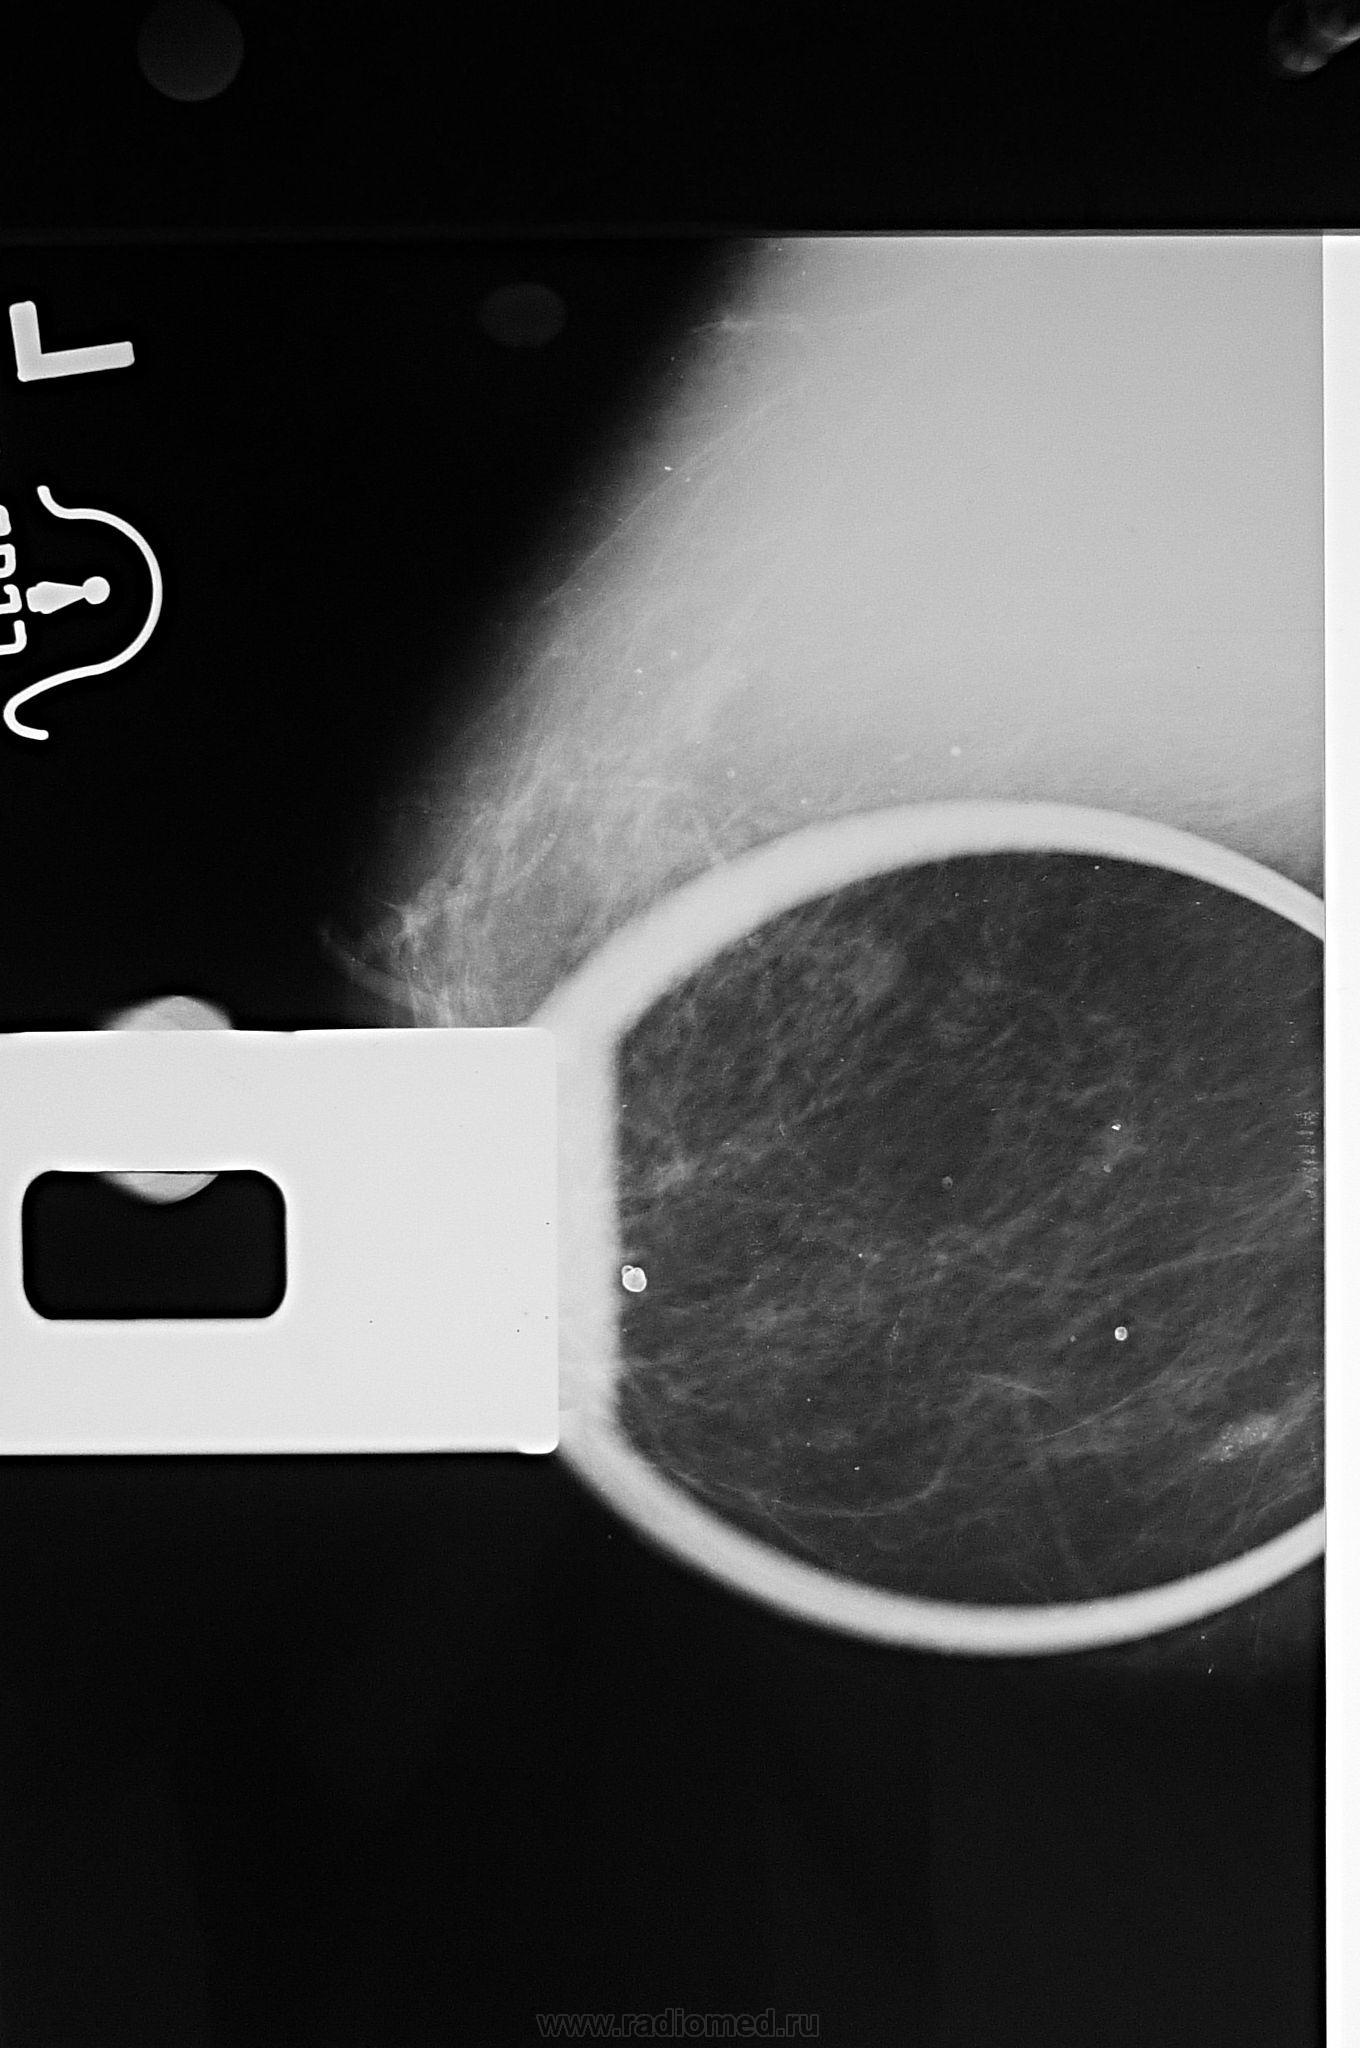

Для снимков с увеличением на вашем маммографе есть приставка и маленький тубус,  железа кладется на столик, режим выбирается вручную, я часто использую 23-125, или 22-100 в зависимости от размеров желзы, очень хорошо видны контуры образования, микрокальцинаты.